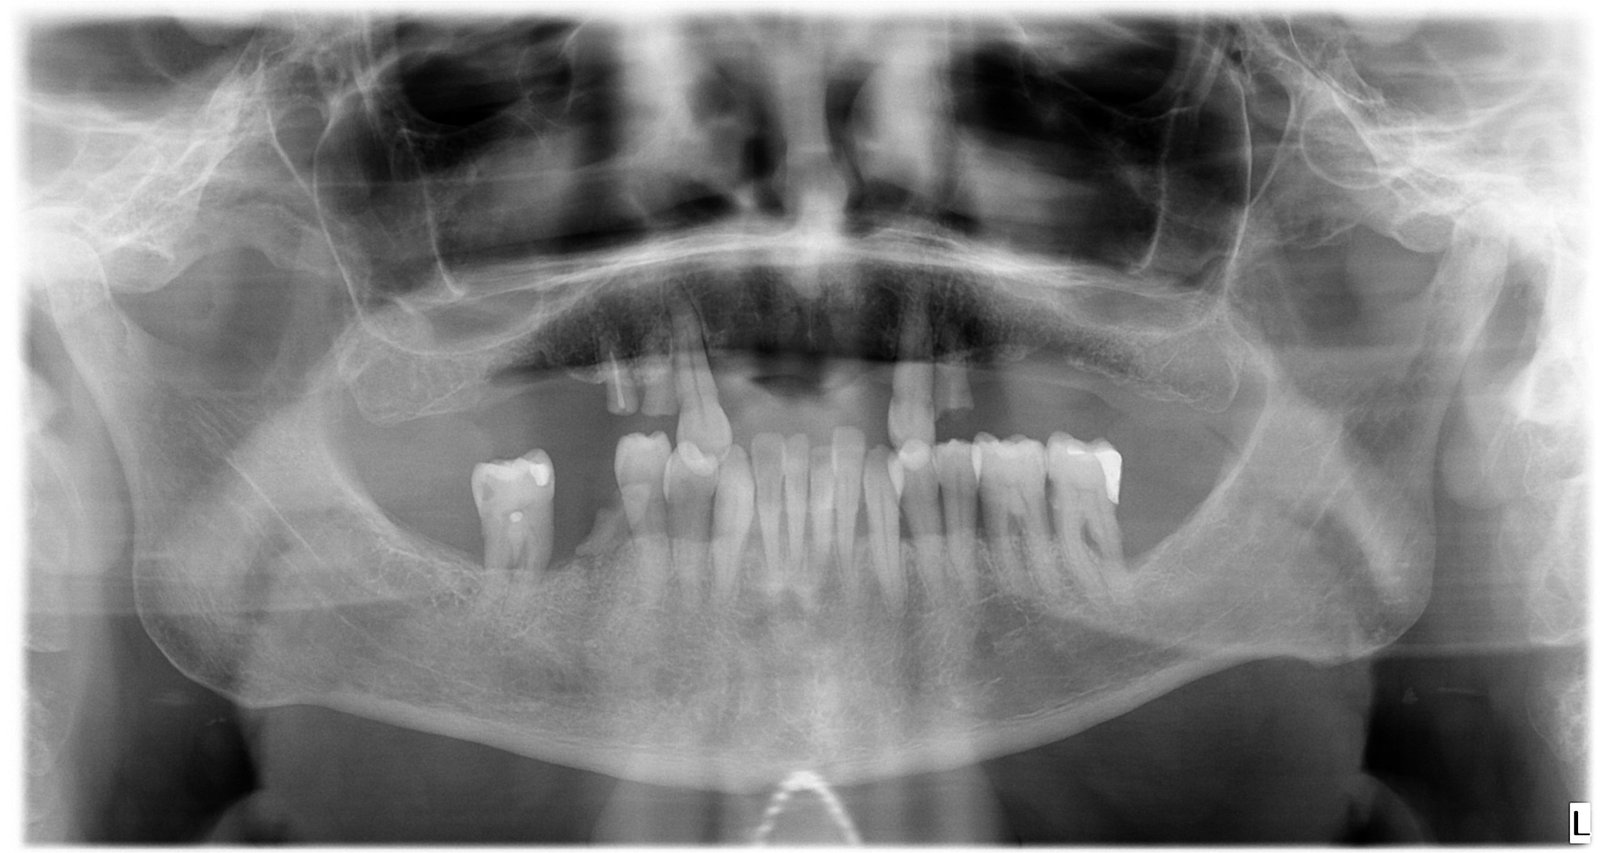

Caso 1 - caso de Implantes dentales

El paciente acudió a consulta con la ausencia de varias piezas dentales que dificultaban la masticación y afectaban a la estética de su sonrisa. Con la colocación de implantes dentales conseguimos recuperar dientes fijos, funcionales y de aspecto natural, devolviéndole seguridad y comodidad al sonreír.

En esta imagen se aprecia la ausencia de piezas dentales y el estado inicial del hueso, lo que permitió planificar un tratamiento implantológico preciso y seguro.